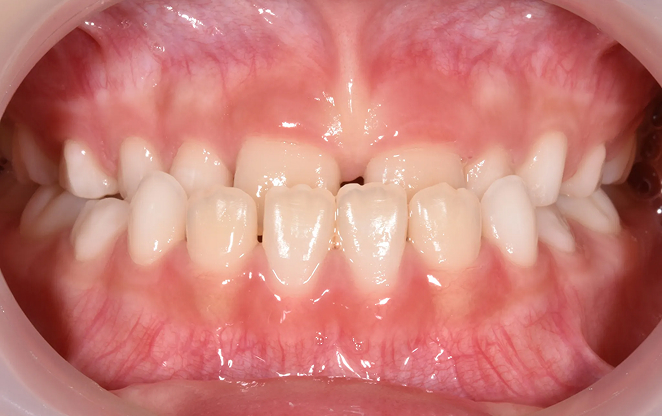

초등학생 1차 교정은 영구치가 나오기 전 혼합치열기에 시작하는

교정입니다. 이 중요한 시기에 치아가 제대로 자리 잡을 수 있도록,

아이의 밝은 미래를 위한 준비를 도와드릴게요.

Before

After